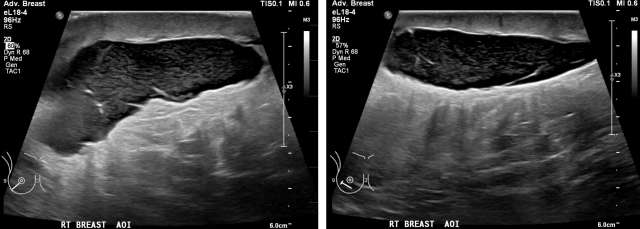

• Mammogram: Water-density masses located at the surgical site, Figure 5.23

Case: Post-Surgical Fluid Collections Figure 5

Figure 5 -Right MLO and CC views demonstrate a mass in the upper outer breast 9 months following lumpectomy and sentinel lymph node biopsy.  Note prominent skin thickening, which corresponds to patient’s lymphedema.